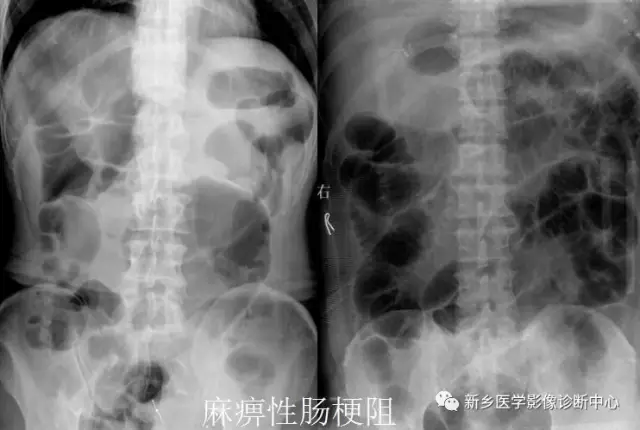

13 肠梗阻

文章图片

1.肠梗阻:中腹部多发阶梯状 , 马蹄状液平 。 2.空肠不全性梗阻 。

1.空肠不全性梗阻:空肠扩展呈弹簧状 。 2.空肠机械性梗阻:弹簧征